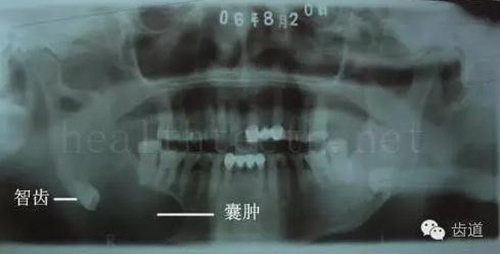

智齒造成的頜骨囊腫,手術(shù)切除后需要植骨

82.jpg